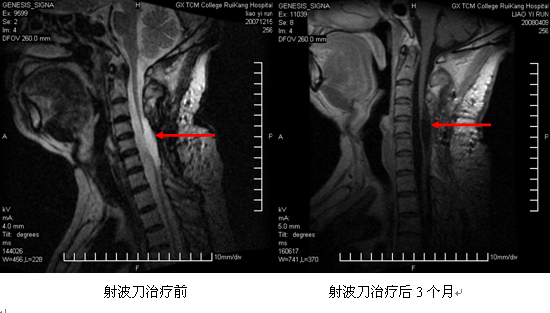

射波刀治疗颈4~6髓内神经纤维瘤病例:男,56岁,因四肢麻木、行走不稳20余年入院。患者20多年来因颈椎髓内神经纤维瘤行5次手术切除治疗,但症状一直反复发作。近一个多月以来患者四肢无力,不能起床,不能独自站立,生活不能自理,复查颈椎MRI提示:颈4~6髓内神经纤维瘤,脊髓明显受压。患者因反复5次手术,对施行第6次手术有恐惧感,故要求行射波刀治疗。患者在我院射波刀中心行5次治疗(每次约1小时,每天1次,连续5天),治疗后患者能自行起床,能自行进食,不需扶助下站立半小时,于治疗后第3天出院。出院后患者症状随时间推移而进行性改善,射波刀治疗后2个多月,患者能生活自理,能独立行走,四肢麻木明显减轻。射波刀治疗后3个月,回院复查MRI提示:颈4~6神经纤维瘤消失,局部囊性变。但患者因脊髓受压明显,嘱其加强功能锻炼以期促进康复。